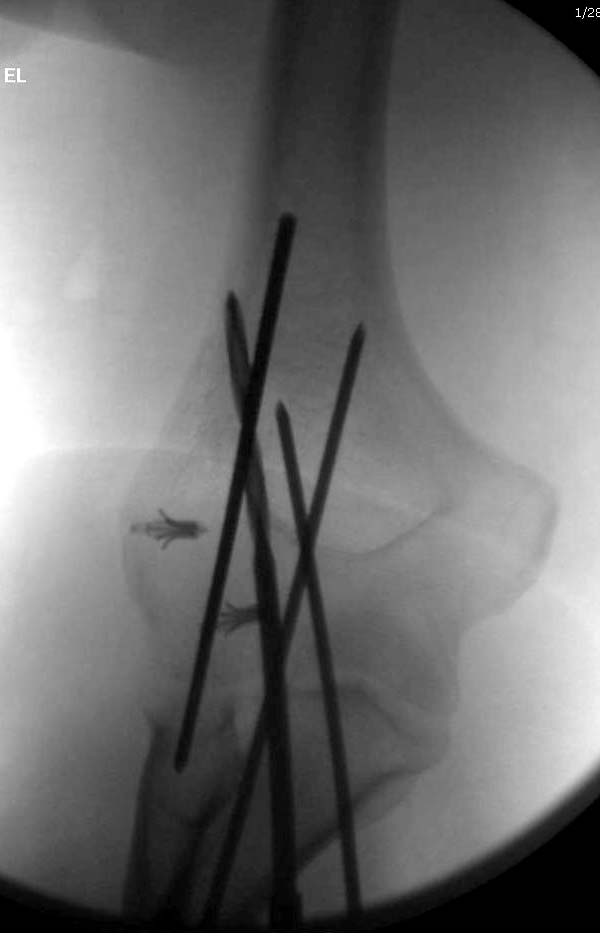

Несмотря на отрицательный отзыв, некоторые нестабильные вывихи лечим трансартикулярным методом. Тонкие спицы ломаются и имеют риск внутрисуставной инфекции. Винты 3.5 мм не выдерживают, а более толстые каннюлированные винты неплохо проявили себя. Неосторожность при установке приводила к поломке тонких guide wire внутри сустава. Лучшие кортикальные в 4.5 мм и гипс на три недели. Винт удаляется, затем разработка сустава.

Иногда гипс не гарантировал стабильность и винт внутри гипса ломался. Удаление сломанного винта облегчаем, оставляя на пару мм длиннее с наружной стороны, Т.е винт через олекранон над наружный мыщелок, и никогда в трубку диафиза! Из малого разреза кончик сломанного винта удаляется без проблем.

Для примера здесь случай начатый в другом центре, а потом переправленный к нам.

Снимки: 1-2 вывих, 4-5 вторичное смещение в гипсе, реконструкция латеральной связки и капсулы 13-14, повторный вывих после реконструкции, перевод в наш центр; 18-21 временная фиксация, 22-25 трансартикулярная фиксация и нестабильная головка фиксирована спицами, 29-30 амбулаторно, 32-33 после удаления винта и спиц...